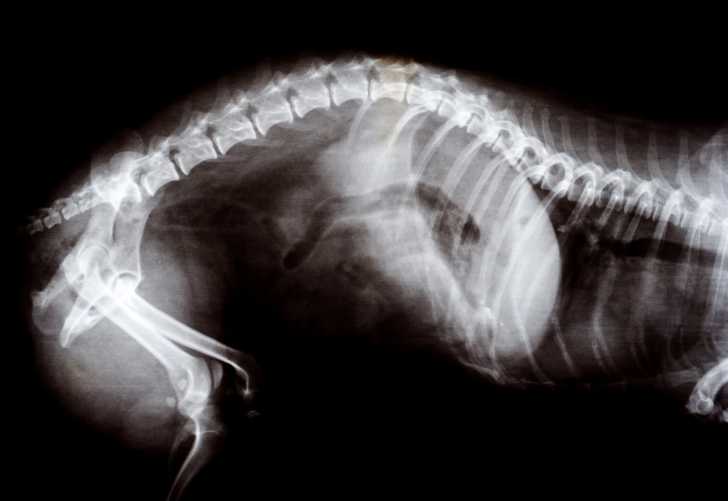

Jour 40 : les papilles olfactives terminent leur croissance et le goût s'affine. Le squelette est bien formé et visible aux rayons X, ce qui permet de déterminer précisément le nombre de petits attendus à l'aide d'une échographie. Les portées de chats comptent généralement 4 à 8 bébés, mais ce nombre peut varier notamment en fonction de la race : par exemple, le Persan et l’Exotic Shorthair ont en moyenne 2 à 3 petits, alors que les plus grandes races de chats, à l'instar par exemple du Sibérien ou du Maine Coon, se rapprochent plutôt des 4 chatons par portée.

Ces examens ont pour but de suivre la croissance des foetus à intervalle régulier, mais aussi de déterminer le nombre de petits dans la portée. En tout état de cause, il est impossible de le faire avant la fin de la 5ème semaine, car ils sont trop petits : leur squelette n'est pas encore bien visible aux rayons X.